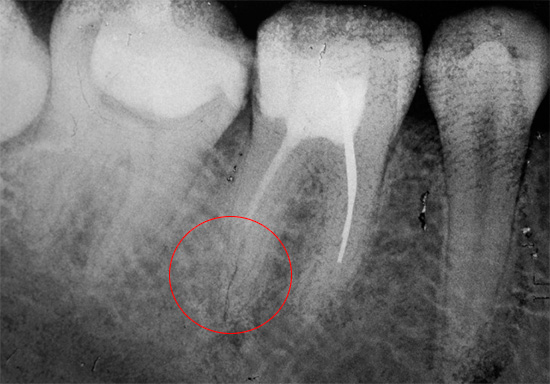

- Riempimento del canale con la rimozione di materiale oltre la radice. Questo errore porta a un dolore di lunga durata quando si preme sul dente, nonostante un riempimento correttamente installato.

- Riempimento del canale non fino all'apice (apice). Il canale dovrebbe normalmente essere sigillato per l'intera lunghezza di lavoro. Se ciò non accade, a un certo punto è vuoto. La natura non tollera il vuoto, quindi, i microbi si accumulano nell'area non sigillata, che successivamente provocano infiammazione alla radice. Alcune persone immediatamente o dopo qualche tempo hanno dolori doloranti sotto il riempimento, o un dente sigillato fa male quando viene premuto su di esso. In questo caso, è necessario ritrattare e riempire nuovamente il canale.

- Strumento rotto nel canale. In questo caso, la complicazione sorge a causa del lasciare un pezzo di uno strumento dentale nel canale con una fonte di infezione - un "nervo" infiammato o con batteri non lavati fuori dal canale. In futuro, questo spesso porta a dolore dopo aver riempito i canali dentali - immediatamente o dopo alcune settimane (a volte anni).

Se tutto il trattamento viene eseguito correttamente, ma il dente fa male dopo aver riempito i canali, ciò significa che si è verificata un'infezione residua nella regione apicale della radice.

Se un dente fa male dopo il riempimento con la pressione, ciò può essere dovuto al trattamento della parodontite, che appare a causa della pulpite avanzata. La parodontite può anche essere causata dal posizionamento improprio di un riempimento nei canali radicolari durante il trattamento della pulpite.